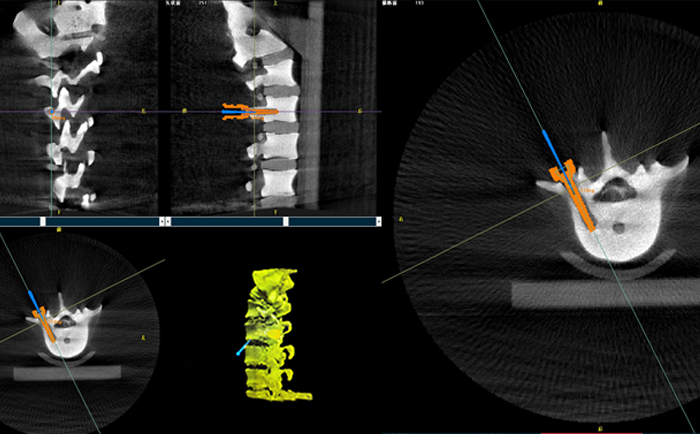

在一臺機(jī)器人輔助下的脊柱手術(shù)中,使用三維C形臂與機(jī)器人匹配,僅15秒左右就能獲得患者病變脊柱部位的高清3D圖像,機(jī)器人輔助手術(shù)可準(zhǔn)確定位病變部位、置入椎弓根螺釘位置等。

目前脊柱外科應(yīng)用最廣泛的還是機(jī)器人輔助置入椎弓根螺釘。主刀大夫可以通過該3D圖像確定手術(shù)中椎弓根螺釘?shù)倪M(jìn)釘點、置釘方向以及置釘深度。緊接著,在機(jī)器人手術(shù)系統(tǒng)的導(dǎo)航下,該機(jī)械手臂能夠準(zhǔn)確移動到定位椎弓根螺釘?shù)戎冕斘恢?,醫(yī)生只需要在置釘部位切開一個1cm切口,沿著機(jī)械臂所指方向鉆入導(dǎo)針,并沿導(dǎo)針按置入椎弓根即可,從而使椎弓根螺釘能夠以最理想化的方式打入,保證患者的安全和手術(shù)有效性。